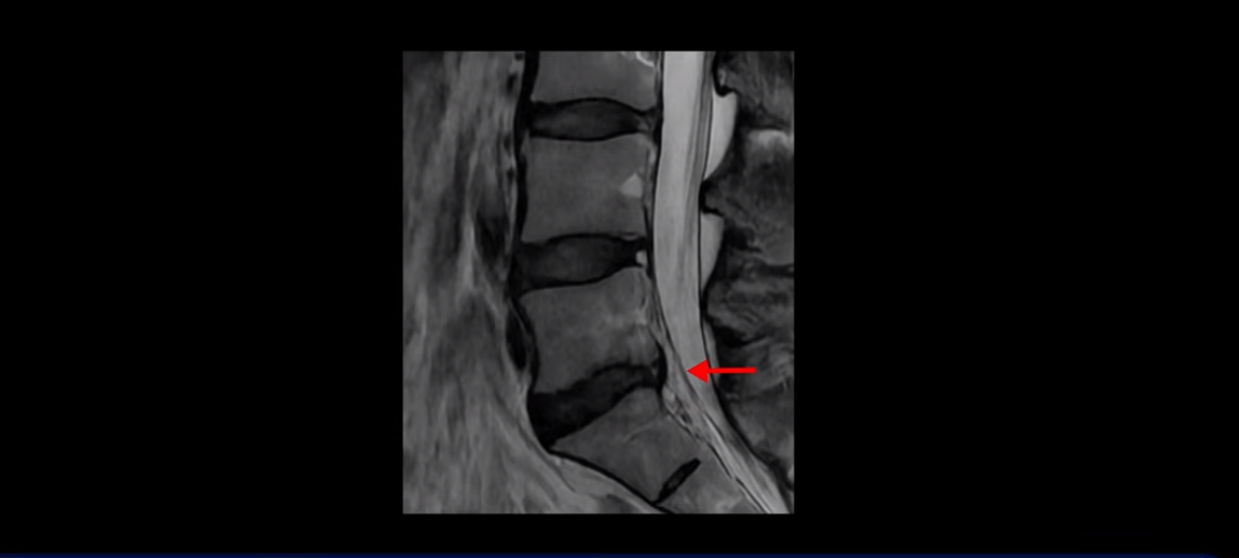

우선 이분 허리 MRI를 보면 5번 1번에 퇴행성 디스크가 있지만 방사통을 일으킬 만큼 신경을 누르고 있어 보이지 않습니다.

오른쪽으로 디스크가 약간 찢어져 보이는데, 작년에 찍은 MRI에서도 보이는 것이라 오래 전에 찢어진 후 아문 흔적으로 보입니다.

중요한 것은 오른쪽 다리에 심한 방사통이 있다든가 재채기를 못 한다거나 허리를 구부리거나 몸을 살짝 비틀 때 날카로운 통증이 없습니다. 즉, 섬유륜이 최근에 찢어진 게 아닌 겁니다.